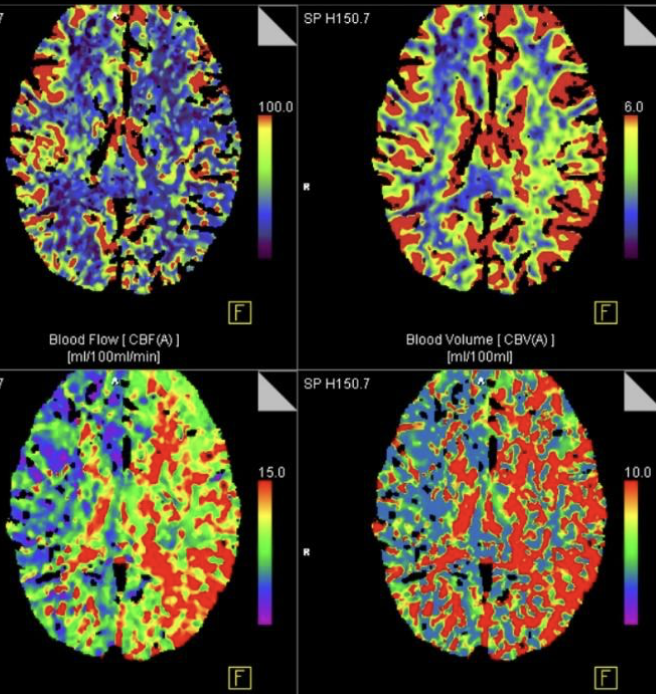

Мр перфузия

Мр перфузия 119 фотографий